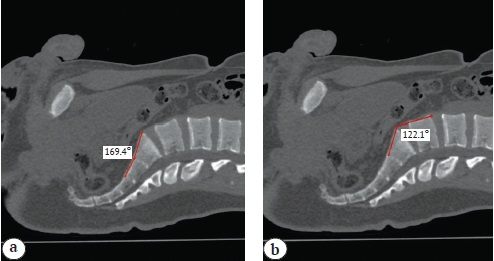

The sacral concavity angle was plotted with the apex on the S1-S2 intervertebral disc along the anterior surface, with the ray coinciding with the anterior surface of the S1 sacral vertebra, and the ray coinciding with the anterior surface of the S2 sacral vertebra (Fig. 3 a).

Fig. 3. Sacral concavity angle (а), promontory angle (b)

The promontory angle was plotted with the apex at the antero-superior edge of the S1 vertebra, with the ray lying on its anterior surface, and the ray lying on the anterior surface of the L5 lumbar vertebra (Fig. 3 b).